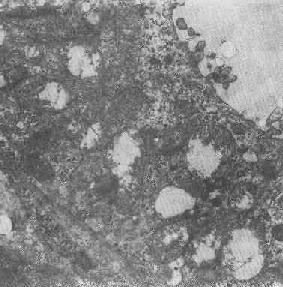

四、线粒体线粒体(mitochondrion)是细胞内主要的能量形成所在,故不论在生理上或病理上都具有十分重要的意义。 线粒体为线状、长杆状、卵圆形或圆形小体,外被双层界膜。外界膜平滑,内界膜则折成长短不等的嵴并附有基粒。内外界膜之间为线粒体的外室,与嵴内隙相连,内界膜内侧为内室(基质室)(图1-8)。在合成甾类激素的内分泌细胞(如肾上腺皮质细胞、卵甾滤泡细胞、睾丸的Leydig细胞等),线粒体嵴呈小管状。内外界膜的通透性不同,外界膜的通透性高,可容许多种物质通过,而内界膜则构成明显的通透屏障,使一些物质如蔗糖和NADH全然不能通过,而其他物质如Na+ 和Ca 2+等也只有借助于主动运输才能通过。线粒体的基质含有电子致密的无结构颗粒(基质颗粒),与二价阳离子如Ca2+及Mg2+具有高度亲和力。基质中进行着β氧化、氧化脱羧、枸橼酸循环以及尿素循环等过程。在线粒体的外界膜内含有单胺氧化酶以及糖和脂质代谢的各种转移酶;在内界膜上则为呼吸链和氧化磷酸化的酶类。 线粒体是对各种损伤最为敏感的细胞器之一。在细胞损伤时最常见的病理改变可概括为线粒体数量、大小和结构的改变: 1.数量的改变 线粒体的平均寿命约为10天。衰亡的线粒体可通过保留的线粒体直接分裂为二予以补充。在病理状态下,线粒体的增生实际上是对慢性非特异性细胞损伤的适应性反应或细胞功能升高的表现。例如心瓣膜病时的心肌线粒体、周围血液循环障碍伴间歇性跛行时的骨骼肌线粒体的呈增生现象。 线粒体数量减少则见于急性细胞损伤时线粒体崩解或自溶的情况下,持续约15分钟。慢性损伤时由于线粒体逐渐增生,故一般不见线粒体减少(甚至反而增多)。此外,线粒体的减少也是细胞未成熟和(或)去分化的表现。 2.大小改变 细胞损伤时最常见的改变为线粒体肿大。根据线粒体的受累部位可分为基质型肿胀和嵴型肿胀二种类型,而以前者为常见。基质型肿胀时线粒体变大变圆,基质变浅、嵴变短变少甚至消失(图1-9)。在极度肿胀时,线粒体可转化为小空泡状结构(图1-10,图1-11)。此型肿胀为细胞水肿的部分改变。光学显微镜下所谓的浊肿细胞中所见的细颗粒即肿大的线粒体。嵴型肿较少见,此时的肿胀局限于嵴内隙,使扁平的嵴变成烧瓶状乃至空泡状,而基质则更显得致密。嵴型肿胀一般为可复性,但当膜的损伤加重时,可经过混合型而过渡为基质型。 线粒体为对损伤极为敏感的细胞器,其肿胀可由多种损伤因子引起,其中最常见的为缺氧;此外,微生物毒素、各种毒物、射线以及渗透压改变等亦可引起。但轻度肿大有时可能为其功能升高的表现,较明显的肿胀则恒为细胞受损的表现。但只要损伤不过重、损伤因子的作用不过长,肿胀仍可恢复。 线粒体的增大有时是器官功能负荷增加引起的适应性肥大,此时线粒体的数量也常增多,例如见于器官肥大时。反之,器官萎缩时,线粒体则缩小、变少。

图1-10肾小管上皮细胞线粒体部分空泡变